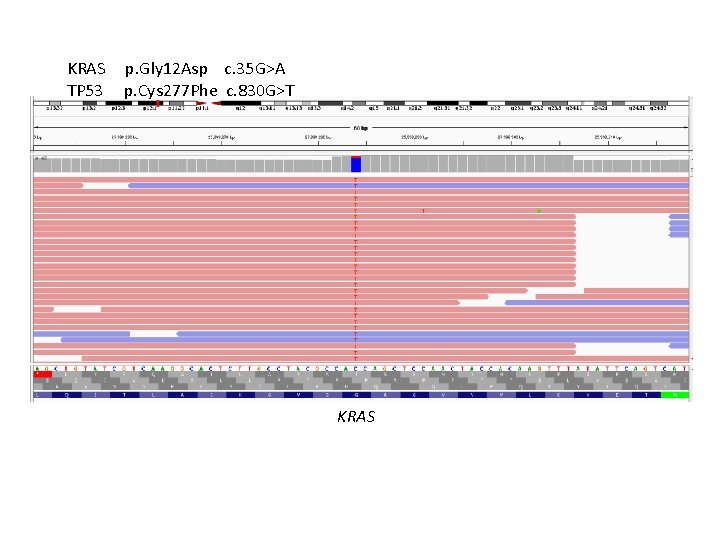

KRAS TP 53 p. Gly 12 Asp c. 35 G>A p. Cys 277 Phe c. 830 G>T KRAS